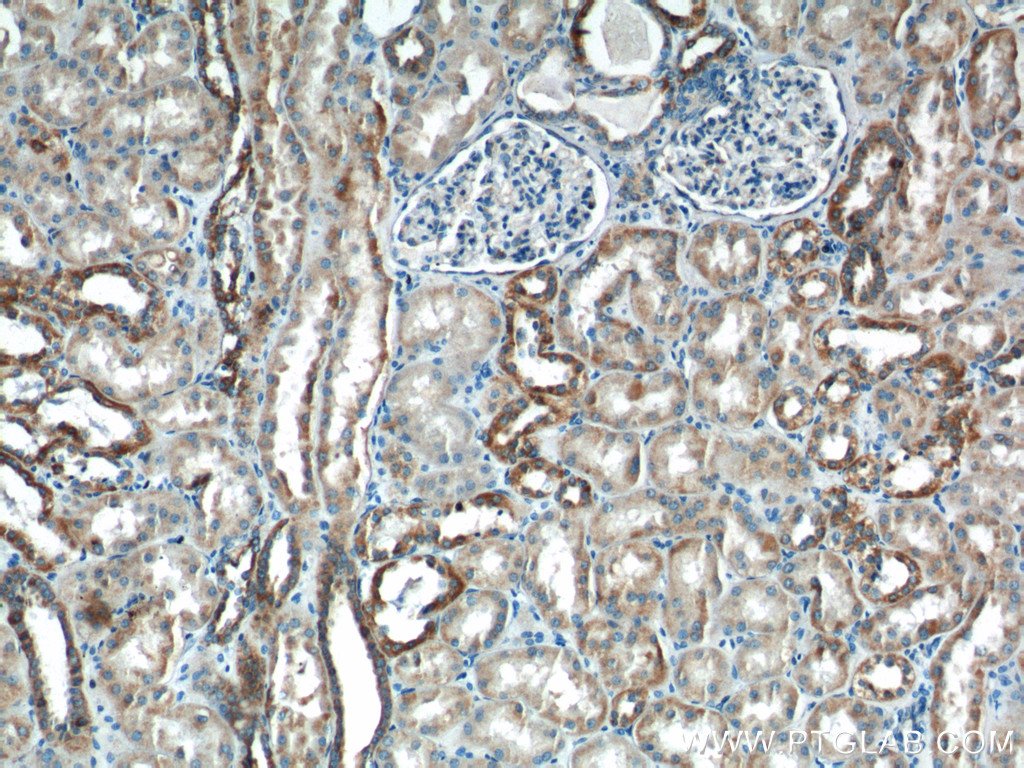

| Positive IHC detected in | human kidney tissue Note: suggested antigen retrieval with TE buffer pH 9.0; (*) Alternatively, antigen retrieval may be performed with citrate buffer pH 6.0 |

| Immunohistochemistry (IHC) | IHC : 1:100-1:400 |